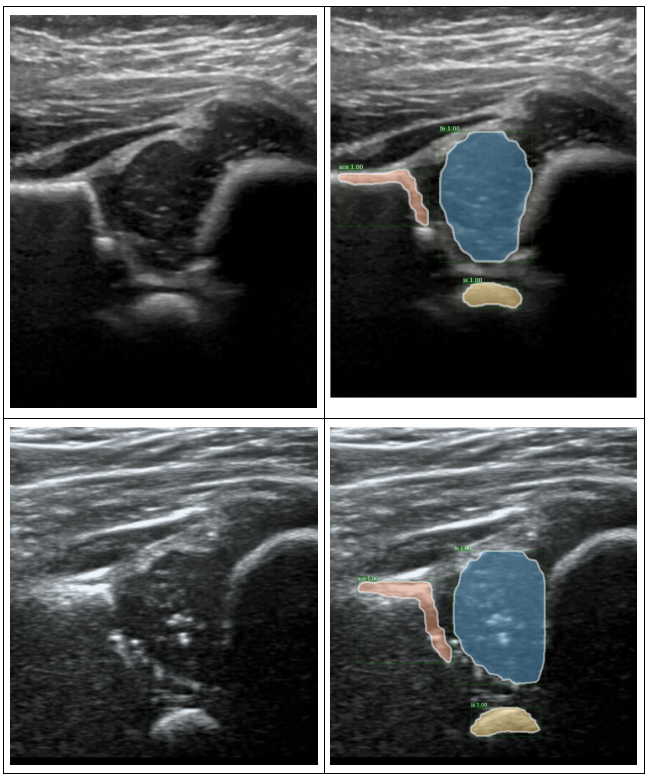

人体髋关节。对每一个人的髋关节有左右两个图像。

目前我们标记的数据,都是从视频中找出左侧骨头最水平的一张,抽出来标记。

Labels:(4个分类)使用labelme标记。